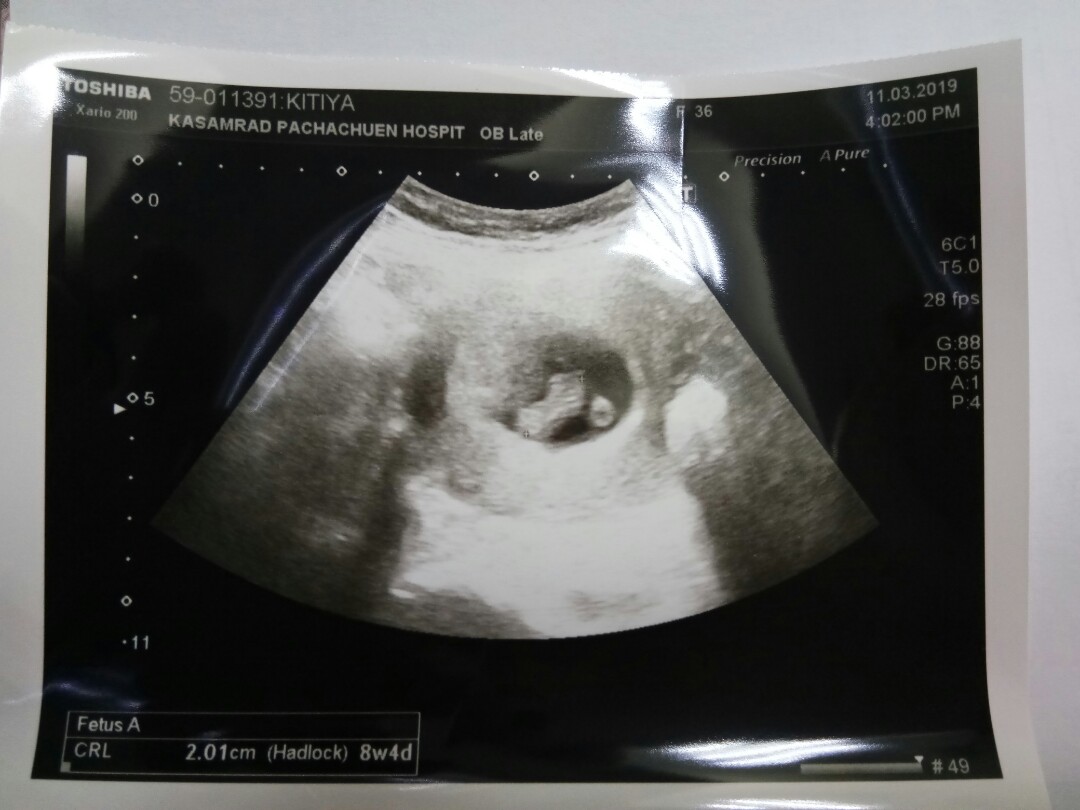

6week ค่ะ เหมือนลูกน้ำเลย

รู้ตัวตอน 2 เดือน ❤❤

ซาวน์ครั้งแรกน้ำตาจะไหลค่ะ